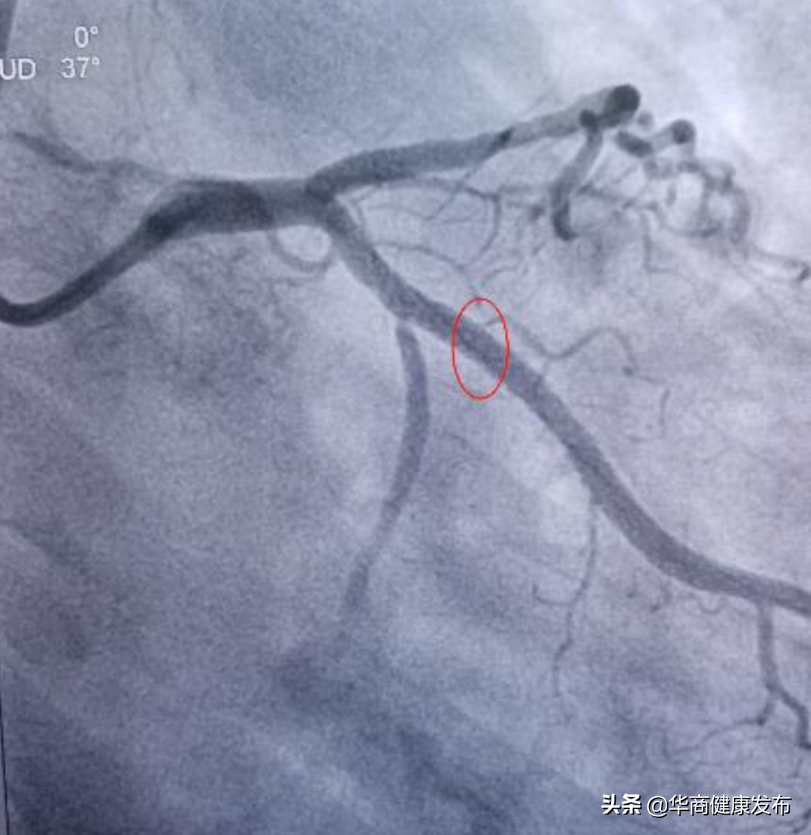

2021年12月27日晚、12月30日、12月31日西安交大二附院整建制医疗二队、三队和重症医学小组共计135名队员分批进驻市人民医院,以加强市人民医医疗救治力量。全体队员深入学习贯彻习近平总书记关于疫情防控工作的重要指示批示精神,认真落实孙春兰副总理要求,坚持人民至上、生命至上,在最短的时间内完成接管病区,在最短的时间让患者得到了有效的治疗。2022年1月13日从长安区医院急诊转入一位54岁男性新冠肺炎合并急性心梗患者,巩守平书记第一时间组织心脏介入团队,启动应急预案,由心内科高登峰教授带队,范博渊医生、李婧和徐一涛护师组成心脏介入应急团队,立即为患者实施CAG+PCI术,35分钟内打通闭塞血管,缓解了患者症状,彰显了交大二院人的高超医技和职业素养,获得了国家专家组及省市卫健委的高度认可。